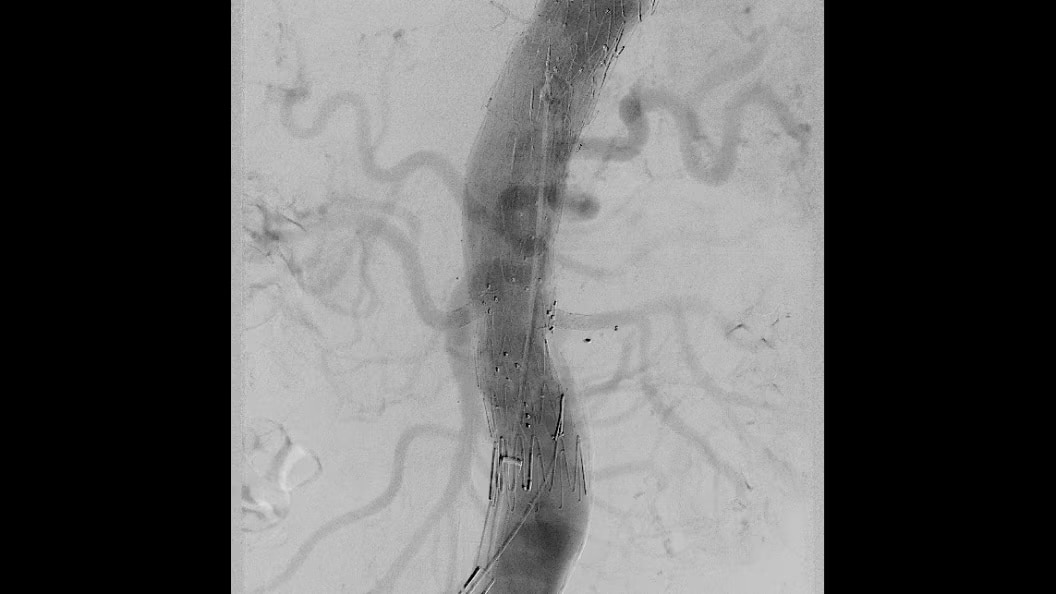

Liver ASSIST Virtual Parenchyma

Liver ASSIST Virtual Parenchyma, powered by Edison, is a 3D Visualization software solution designed to provide AI based virtual parenchymography to help you simulate injections dynamically and thus, perform liver embolization procedures with confidence.